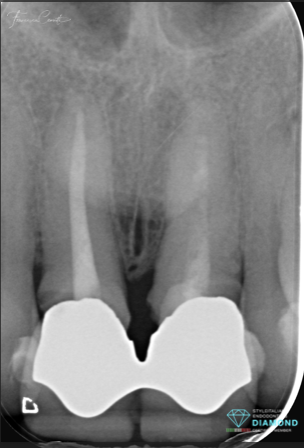

Fig. 1

Pre operative situation:

The patient presented with two defective crowns, with secondary decay, that had been that way for several years.

Considering the extension of the decay, the time of the exposure of the root canal filling to the oral environment and the quality of the existing root canal treatments, the following treatment planning was formulated: